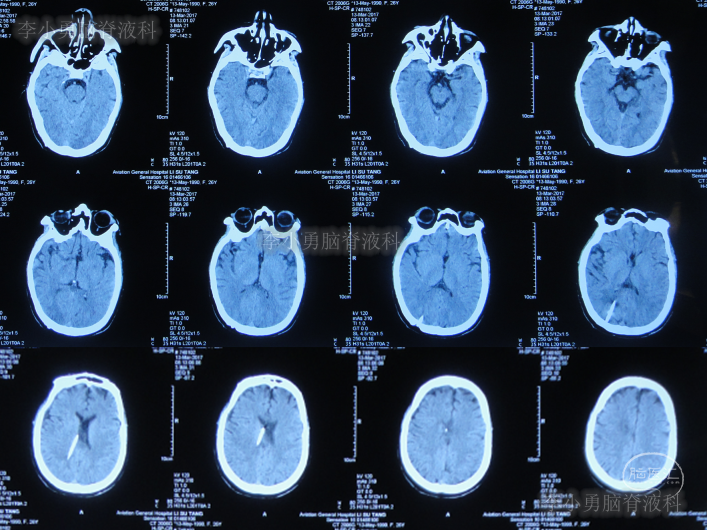

家属为进一步明确病因即2016年4月4日,第2次就诊并住入第二家的上海市静安区的某三甲医院,复查头颅影像后(图-3、图-4),给予按癫痫进行治疗。

图-4:2016年4月4日头颅影像